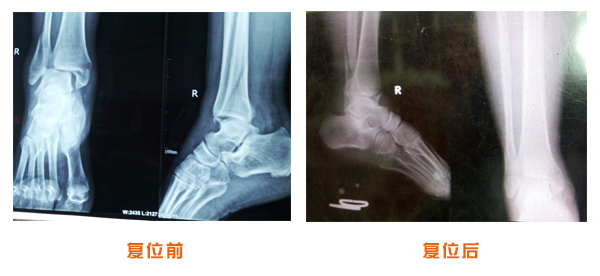

復位前后對比

尺橈骨克雷氏骨折治療前后